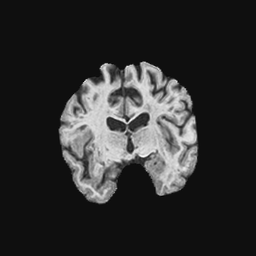

Exp. 1: Segmented adult brain data is used to evaluate our network’s regression performance with known ground truth Tisubscript𝑇𝑖T_{i}. 85 brains from the ADNI data set[1] were randomly selected; 70 brains for ΩtrainsubscriptΩ𝑡𝑟𝑎𝑖𝑛\Omega_{train} and 15 brains for ΩvalidationsubscriptΩ𝑣𝑎𝑙𝑖𝑑𝑎𝑡𝑖𝑜𝑛\Omega_{validation}. Fig. 2 shows an example slice of the ground truth and the reconstructed ΩΩ\Omega.

Figure 2: Example slice from the segmented adult brain MRI data set (a); reconstruction from 300 ωisubscript𝜔𝑖\omega_{i} based on SVRNet regression without SVR (b); SVR initialised with SVRNet predictions after eight iterations of SVR (c). Note that SVRNet (b) predicts individual slice transformations only from image intensities without any initial world co-ordinates of the sampled slice. (d) shows the achieved PSNR in dB when comparing the volumes of (b) and (c) to (a).

Reconstructing from Ti^^subscript𝑇𝑖\hat{T_{i}} initialisation without SVR yields a PSNR of 23.7 ±plus-or-minus\pm 1.09; with subsequent SVR the PSNR increases to 29.5±plus-or-minus\pm2.43 when tested on 15 randomly selected test volumes after four iterations of SVR.